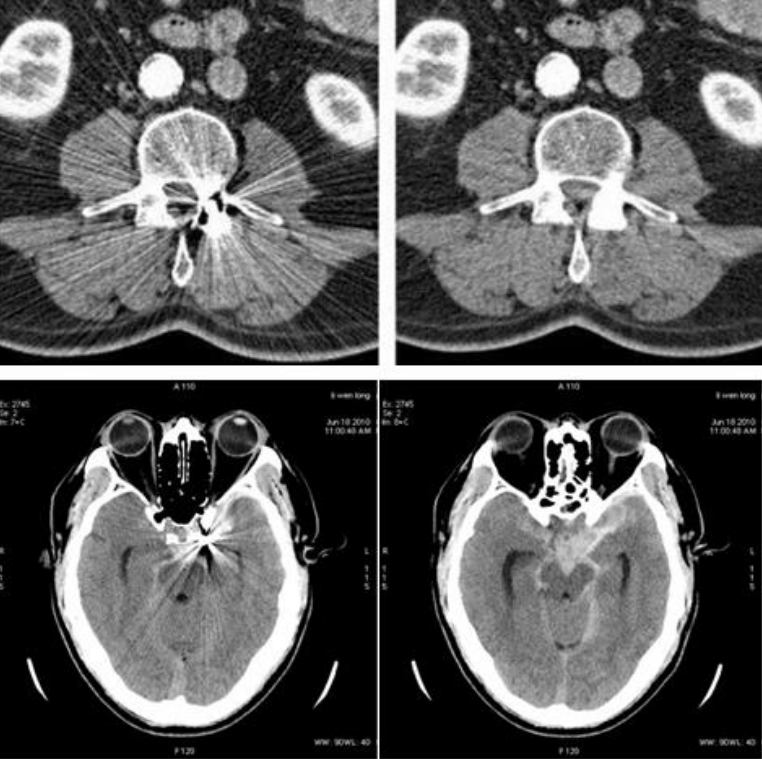

无限制一站式脑卒中成像是指一次造影剂注射、一次扫描,同时完成头颅平扫、头颈CTA、颅脑多期增强和全脑灌注成像。

根据病人发病时间,Revolution CT提供两种一站式脑卒中解决方案:一是发病6小时以内,采用5分钟方案。即在5分钟内完成头颅平扫、头颈CTA和全脑多期增强的检查,评估颈动脉狭窄和侧支循环情况,为制定血管内治疗提供有用信息;二是发病6-24小时,采用10分钟方案。即在10分钟内完成头颅平扫和全脑灌注的扫描,将头颈CTA融入全脑灌注扫描中,并从灌注数据中得到全脑多期增强数据,同时完成头颈CTA、全脑多期增强和全脑灌注信息,评估狭窄、侧枝循环和全脑灌注状态。

GE病人列表怎么删除​【院之重器】GE Revolution 256排超高端CT:让诊断更快,更精准!_https://www.jmylbn.com_新闻资讯_第1张GE病人列表怎么删除​【院之重器】GE Revolution 256排超高端CT:让诊断更快,更精准!_https://www.jmylbn.com_新闻资讯_第2张

一站式多部位联合成像对于脑卒中的快速诊断、分流缺血性卒中患者带来有效的解决方案。更快速地鉴别出血性与缺血性脑卒中,进而加速救治流程,为患者的救治争取更多时间。